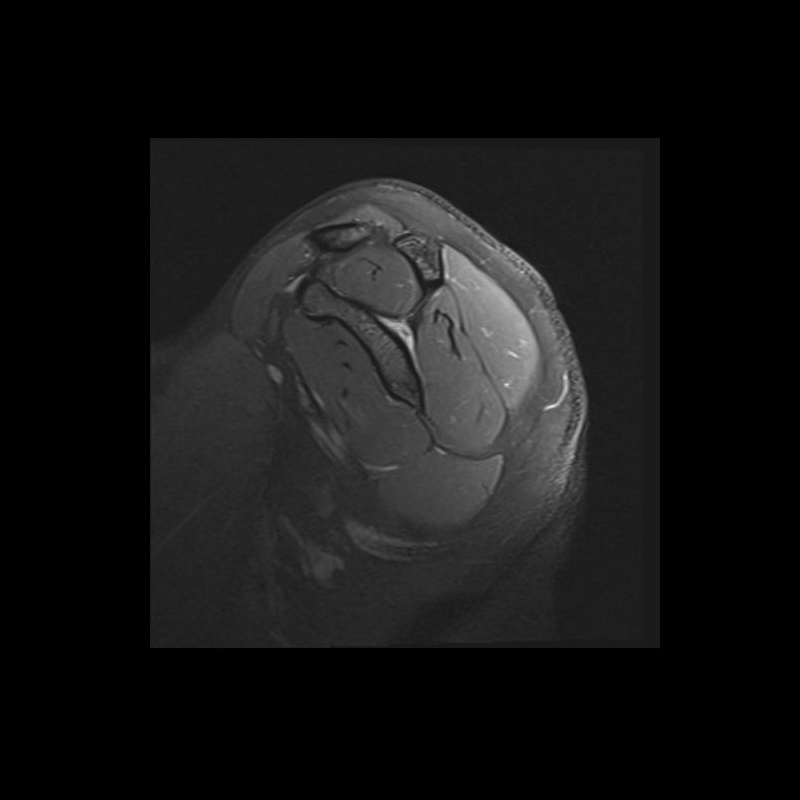

Shoulder MRI Anatomy